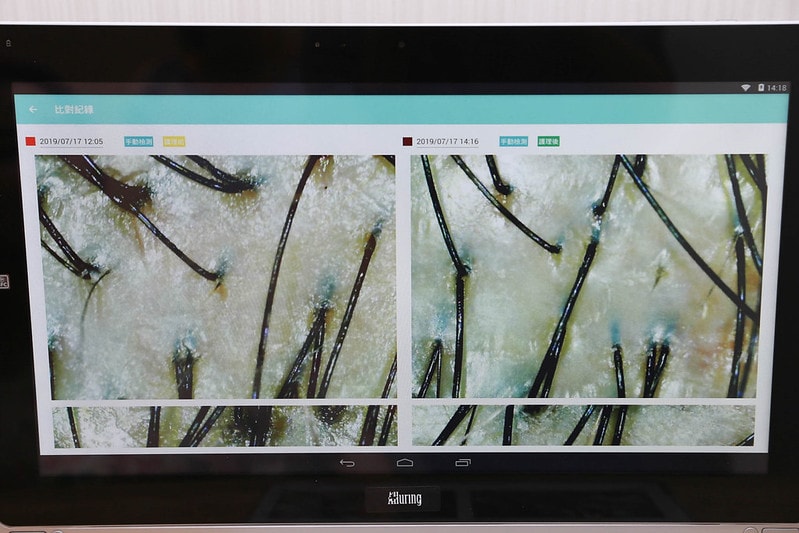

整個課程結束之後

最後還會有一次檢測時間

來看看課程後的頭皮狀況變成怎麼樣

其實這樣一比較起來,就發現真的乾淨很多

頭皮的肌膚變得比較Q彈跟光亮

毛孔堆積的皮脂也潔淨許多

頭皮跟臉皮同屬一張皮

需要好好定期去角質及養護

養好肌底,才能打造澎鬆健康髮